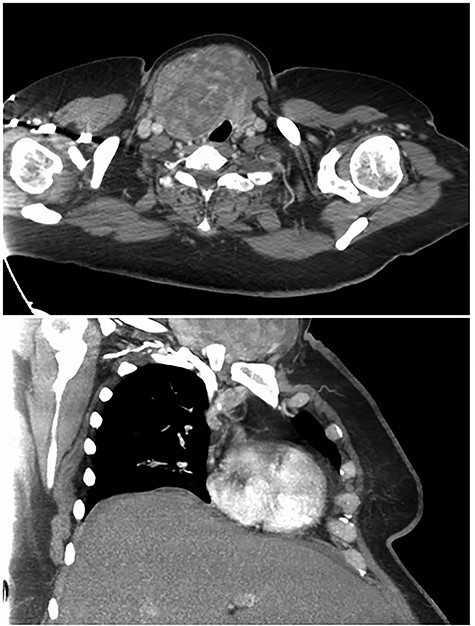

At initial presentation, she was undergoing chemotherapy but recently discontinued one of the agents due to thrombocytopenia. Initial work-up included thyroid-stimulating hormone and free T4 which were within normal limits. A surgeon performed thyroid ultrasound revealed a large 8.9 × 5.0 × 9.7 cm solid, isoechoic, homogeneous nodule without calcifications encompassing the right thyroid lobe and extending into the substernal/subclavicular location (Fig. 2). Fine needle aspiration of the large nodule revealed colloid and follicular groups consistent with colloid nodule or goiter. Given the large size and associated decreased diagnostic accuracy as well as tracheal deviation, excision was recommended after completion of her course of chemotherapy.

Preoperative surgeon performed right thyroid ultrasound images in longitudinal axis (a) and in transverse view (b). The large nodule measured 8.9 × 5.0 × 9.7 cm.